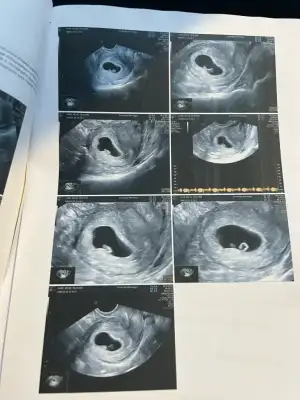

bende bugün ilk kontrolüme gittim , kalp atışı ve bebeği görmek için henüz erken , 10 gün sonra gelin dedi . Kesenin ortasındaki beyazlık bebeği besleme kanalı dedi . Beyazlık kenarındaki küçük beyaz nokta da sanırım bebek , doktor böyle söylemedi ama Banu Çiftçi videosunda öyle söylüyordu ortada pırlanta yüzük görürsünüz , yüzük kısmı yolk kesesi , pırlanta kısmı bebek diye

son adet tarihine göre 5+4 tü , ancak yumurtlamaya göre 5+6 dı . Cihazda yumurtlamaya uygun çıkardı sanırım .bolca süt ürünleri yememi söyledi yoğurt kefir gibi .